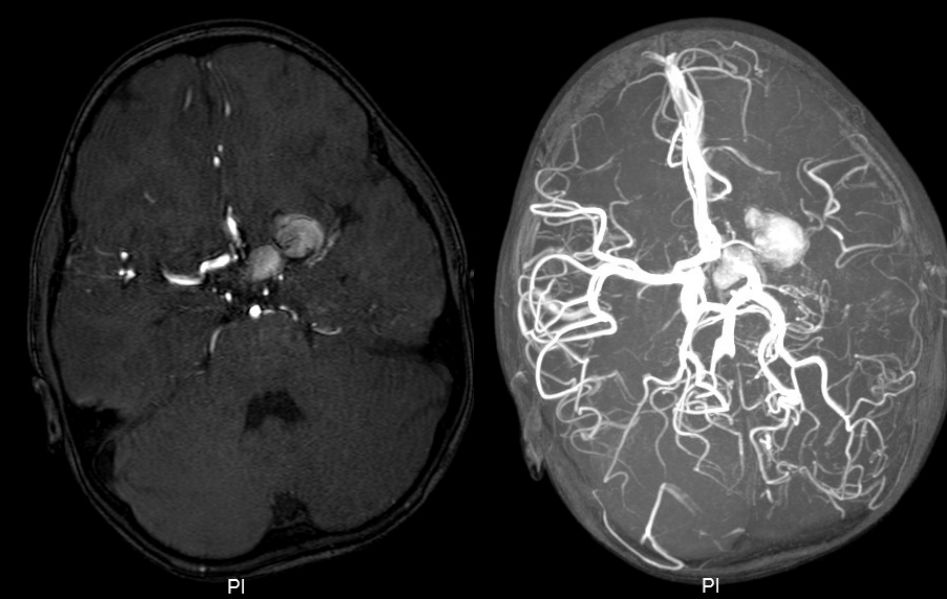

患儿术后情况良好,无对侧肢体偏瘫及其他脑缺血并发症。术后1周复查MRA,提示左侧大脑中动脉M1及大脑前动脉A1段显示欠清,瘤体仍大小相仿(图5)。出院继续随访。

![]()

图5. 术后1周MRA,显示左侧A1和M1纤细,动脉瘤影变淡。

术后1月复查MRA提示:动脉瘤体内类似血栓形成,中动脉周围可见细小侧枝循环血管形成,中动脉远端血管稀疏(图6)。

图6. 术后1月MRA,动脉瘤体内类似血栓形成,中动脉周围可见细小侧枝循环血管形成,中动脉远端血管稀疏